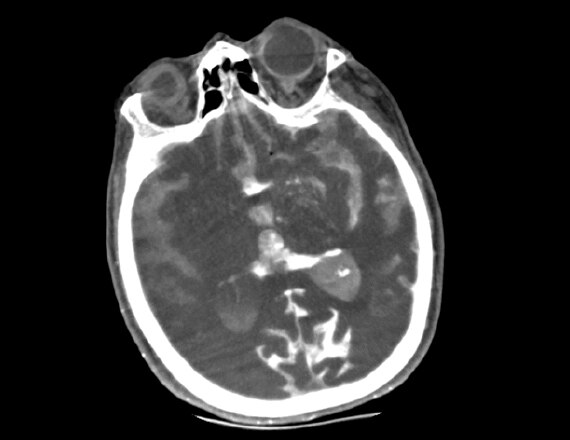

A patient with suspected TIA or stroke receives a general and neurological examination followed by diagnostic brain imaging, performed immediately on arrival so that treatment can be started promptly. 3 Optimal scanning coupled with workflow applications and protocols designed for stroke help deliver accurate and quick diagnosis to impact patient outcomes.

Revolution brand of CT systems

Capable of acquiring neuro perfusion and CTA of the brain in a single exam to enable comprehensive functional and anatomical assessment. Read More

FastStroke CT Application

Simplifies and organizes CT images for fast evaluation of Stroke patients. Read More

Fast Brain protocol with HyperWorks

Providing structural as well as vascular information with improved resolution and precise characterization in 5 minutes. Read More

Acute ischemic stroke is a complex disease and successful endovascular treatment is based on the comprehensive ability to rapidly integrate multiple pieces of information.4 Initiate Intravenous thrombolysis (IV-tPA) if less than 5 hours of ischemic stroke. Initiate mechanical thrombectomy within 6 hours of onset of large vessel stroke (MCA territory). Fast interventions with accurate imaging can help reach lesions quickly to help improve patient outcomes.